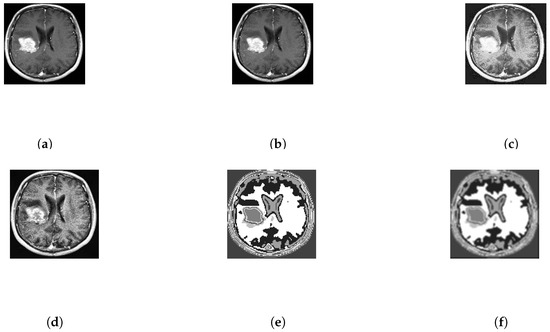

After that, different features are initially extracted implicitly. Every portion of the brain tumor must be selected even a small portion of the brain tumor are not avoided. At frist, the input image is processed through some filter that are described in Figure 3. Then, in Figure 3e, there is initial segmentation of the image using template based K-means (TK) which is segmented on the basis of there gray level intensity and temper of color where k = 8. After that the tumor is filtered by median filter again. Then, the tumor is detected and marked it as red line using improved FCM algorithm based on the Euclidean distance from cluster centre to each data point which primarily depends on the different features. This could be important to grasp the importance of this changed and incorporated technique.

Figure 3.

Processing and Enhancement of the input image no. 10 of database 2. (a) Input image; (b) Adjusted Image; (c) Histogram based Image; (d) Adaptive Histogram Based Image; (e) T-means segmentation; (f) Median filtered image.

Depending on the grey level intensity the improved FCM is performed for 13 clusters. Clustered image is defined as the image with its smallest gray level and separated from each other with their successive color intensity. For instance, many clustered images for input image no. 10 of database 2 are shown in Figure 4. Here, the tumor portion with different portion of the image are shown in individualize image and from this, depending on features the tumor is chosen. Here, the index no. 8 is chosen technically and marked as red line in Figure 5d. Figure 5 shows the input image no. and 20 of database 1 and image no. 10 and 15 of database 2 are shown in Figure 5a and their outputs in Figure 5d respectively.

Figure 4.

Several clustered images for input image no. 10 of database 2.